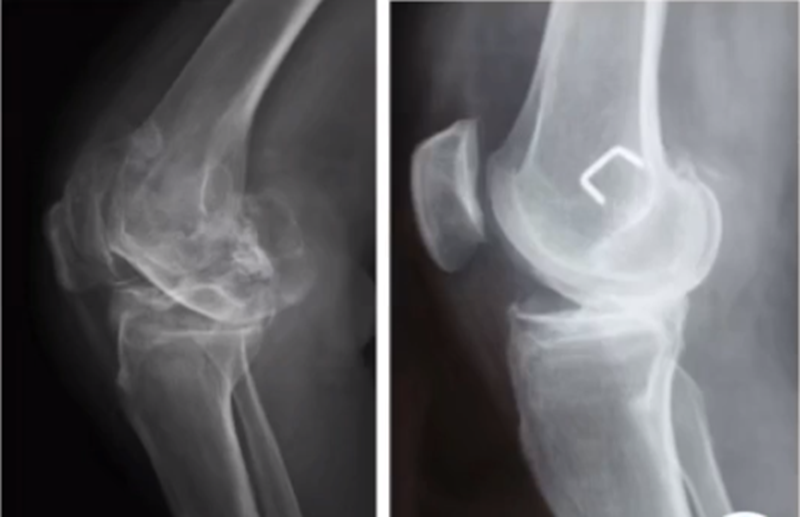

牛津单髁影像学判断的标准为通过负重正位片来判断内侧间室关节软骨的磨损程度。内侧间室关节间隙变窄,股骨内侧髁与内侧胫骨平台成“骨磨骨”状态,说明内侧间室软骨磨损丢失。如果没有在正位片观察到“骨磨骨”,则需要通过内翻应力位片或rosenberg位检查,找到骨磨骨的证据。如果以上均没有显示骨磨骨,需考虑关节镜检查,只有在达到“骨磨骨”的情况下才考虑行UKA。

AMOA查体与X线特点,站立位屈曲内翻

AMOA的X线正位的表现